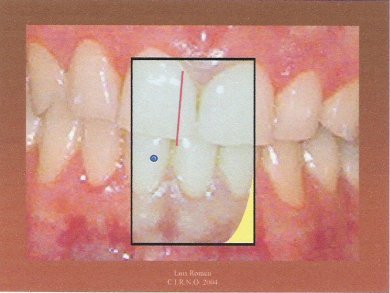

7.- El resultado final nos indica tanto los grados de los ángulos como los milímetros de desplazamiento.

Con muy ligeras modificaciones de este procedimiento se pueden medir los AFMP en casos más complicados como mordidas profundas, mordidas cruzadas anteriores, bocas con pistas, mordidas abiertas, etc.